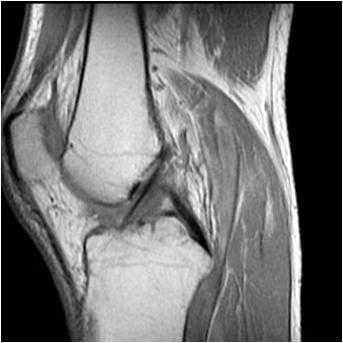

МРТ коленного сустава. Т1-взвешенная сагиттальная МРТ. Крестообразные связки в норме.

Крестообразные связки расположены внутри сустава. При МРТ коленного сустава можно проследить, что ПКС начинается от задне-медиального края латерального мыщелка бедренной кости и прикрепляется к большеберцовой кости кзади от её переднего края, сразу кпереди и латеральнее медиального межмыщелкого выступа. Длина ПКС около 3,5 см, диаметр около 1 см.

ЗКС, как видно при МРТ коленного сустава, начинается от латеральной поверхности медиального мыщелка бедренной кости и крепится к суставной поверхности плато большеберцовой кости. Как и ПКС, она расположена внутри сустава, но вне синовиальной оболочки. Связка в 2 раза мощнее ПКС и тесно связана с мениско-феморальными связками (Ризберга и Хамфри)